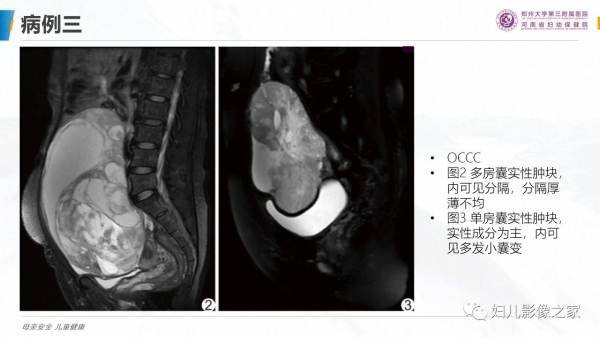

卵巢透明细胞癌

病史:患者女,57岁

主诉:尿频2月余,发现盆腔囊肿4天

现病史:2月前出现尿频尿急,4天前于当地医院彩超发现盆腔囊肿,无女性生殖器官出血,无腹痛

专科检查:于耻骨联合上方可触及拳头大小肿物